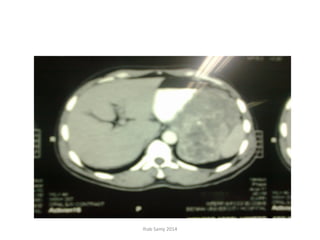

• CT Abdomen and pelvis (13-11-2011): Large

oblong retroperitoneal cystic collection at left

iliac region extending to left lumbar region

measuring 22 X 5 X4 cm. Extending sup. To

reach lower pole of spleen, displacing lt.

kidney medially + multiple enlarged inguino-

iliac LNs 1-3.5 cm. in diameter.

• Follow- up CT Abdomen and pelvis (07-12-

2011): Progressive course since the last study

regarding the left ilio-lumbar cystic mass and

stationary course of lymphadenopathy.